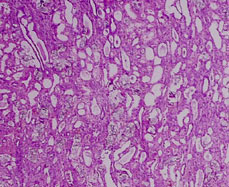

This is a low power view of the corticomedullary junction.